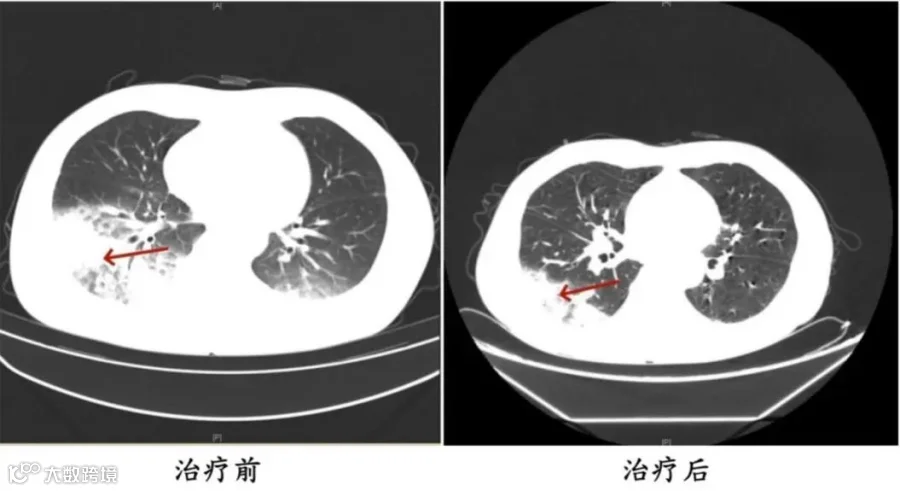

李先生肺部治疗前与治疗后的对比

据报道,李先生开了3天空调后,出现了肌肉酸痛、头痛、发热和咳嗽等症状。起初,他以为是吹空调吹感冒了,于是自行服用感冒药,但病情并未好转,反而愈发严重。家人见状,立即将他送往成都市第五人民医院感染性疾病科。胸部CT显示李先生的左肺已出现大面积白色影像,几乎占据一半肺部。经过肺泡灌洗NGS检测,最终确认“罪魁祸首”是嗜肺军团菌。